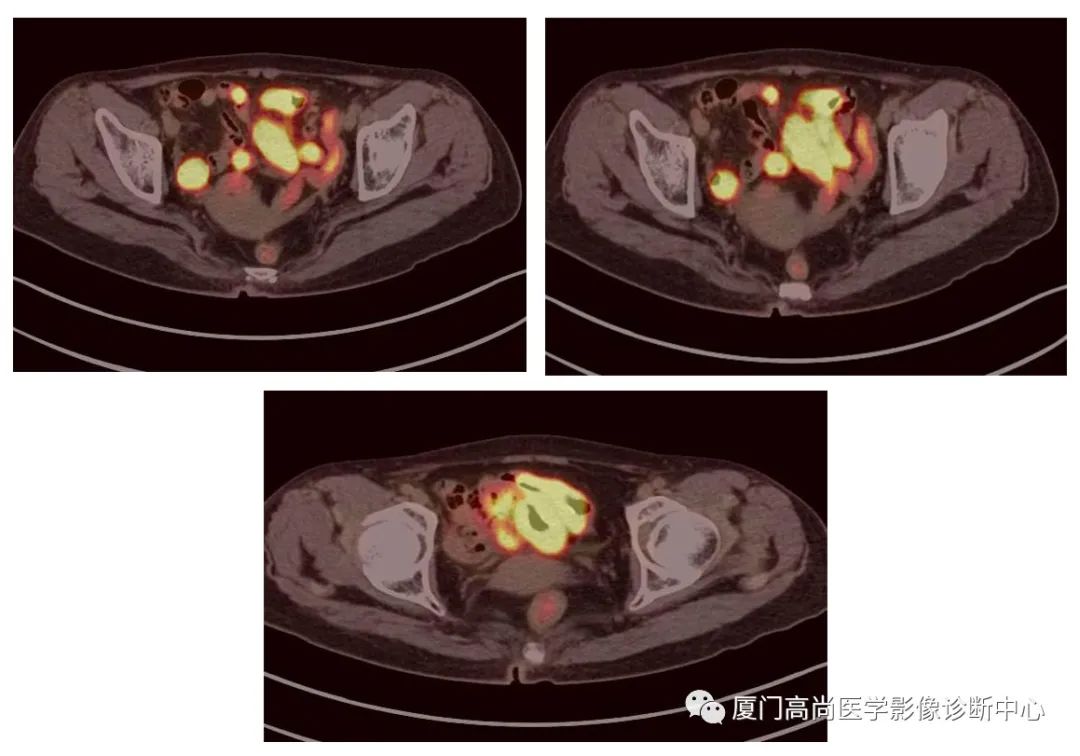

病例2、某女士,62歲,近3個月來自覺消瘦,無其他自覺癥狀,CT發(fā)現(xiàn)雙側(cè)腎上腺增大,性質(zhì)待定,查血各項腫瘤標(biāo)記物均正常,臨床診斷不清,申請做PET/CT檢查

腹腔淋巴結(jié)腫大

小腸多段淋巴瘤病灶

PET/CT發(fā)現(xiàn) :左心房、右心房見團塊狀FDG攝取增高;雙側(cè)腎上腺增大,F(xiàn)DG攝取增高;膽囊和胃壁結(jié)節(jié)樣FDG攝取增高;小腸多節(jié)段腸壁增厚,F(xiàn)DG攝取增高;腹膜后、腹腔及盆腔多發(fā)淋巴結(jié)腫大,F(xiàn)DG攝取增高;上述考慮為淋巴瘤

經(jīng)腎上腺穿刺活檢 :病理證實為彌漫大B細胞淋巴瘤